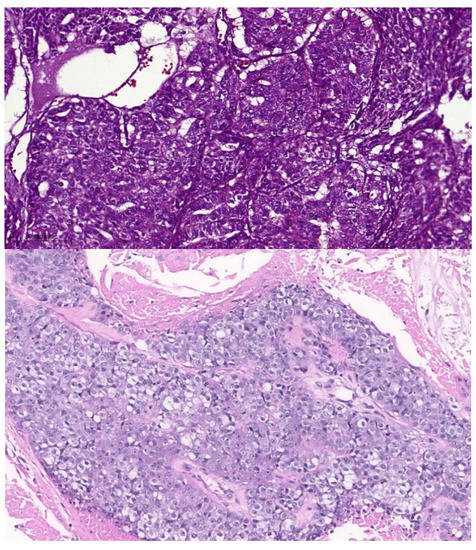

Most of the reported ASCs contained dense squamous congregations intermingled with true duct structures that showed cellular atypia. The stromal adenocarcinomatous component must be neither too superficial and inconspicuous (so as not to be considered an adenoid squamous cell carcinoma) nor very deep (so as not to be considered invasive SCC) (Figure 2). These cases are always considered high-grade. MACs are considered ASCs without an overlying SCC. For example, adnocarcinomatous lesions that secrete mucin and do not align with a particular recognized morphology (e.g., HG-MEC or high-grade mucinous cystadenomacinoma) are considered MACs. The indicated diagnostic immunohistochemical panel is rarely investigated. Figure 4 compares a case of MACs with a high-grade MEC of the minor salivary gland. Figure 5 shows a case of low-grade MAC of the lung. On the other hand, the ASCs of breast show both low-grade and high-grade features (Figure 6).

Figure 4. MAC of the lung.